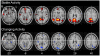

Figure 1. Longitudinal Patterns of Default-Mode Activity

Legend: Top row illustrates default-mode regions commonly active during the resting state relative to task performance at years 1 and 9; these regions also show relative stability of rest-specific rCBF levels over time. Bottom row illustrates rest-specific regions that are active exclusively in years 1 or 9 and also show a significant increase (red) or decrease (blue) in resting-state relative to task-related rCBF levels over time.